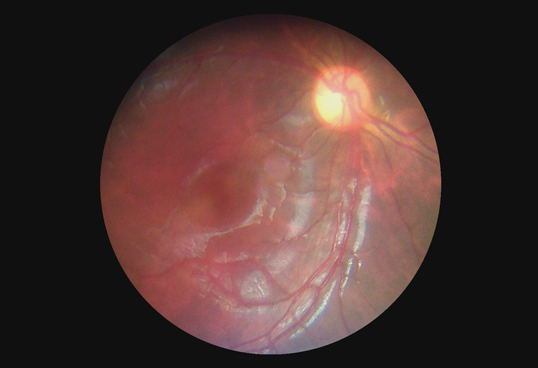

Eye Diagnosis Equipment to See Fundus Diseases Digital Fundus Camera Opthalmoscope WIth 3.5" Touch Screen

It’s said that a picture is worth a thousand words in the physician’s notes.

The pictures taken by fundus camera are visual records which document the appearance of a patient’s retina.

The physician can check a patient’s retina, identify retinal changes on follow-up, or consult a patient ’s retinal findings

with other professionals. Therefore, the quality of fundus image plays a very crucial role during diagnostic process.

BS4 Upgraded, the Digital Handheld Fundus Camera is currently the only portable fundus camera that delivers

45 degree FOV and true 5MP (2592*1944 pixels) of fundus images for health care professionals at all locations

including hospitals, clinics, health screening centers and mobile medical stations.

In addition to excellent image quality that offers more details, the non-mydriatic operation, auto-focus function

and Wi-Fi compatibility of BS4 Upgraded provide not only convenience, but also efficiency for multiple healthcare practices.

The light and compact design of BS4 Upgraded makes screening and documentation of retinal conditions

like AMD, Glaucoma and Diabetic Retinopathy easier than ever before. As a simple to use Digital Handheld Fundus Camera,

BS4 Upgraded enables cost-effective fundus image capture, and is ideal for early diagnosis, telemedicine, mobile care

and outreach activities.

Through the scope

Eye Diagnosis Digital Fundus Camera Equipment To Fundus Diseases Images |